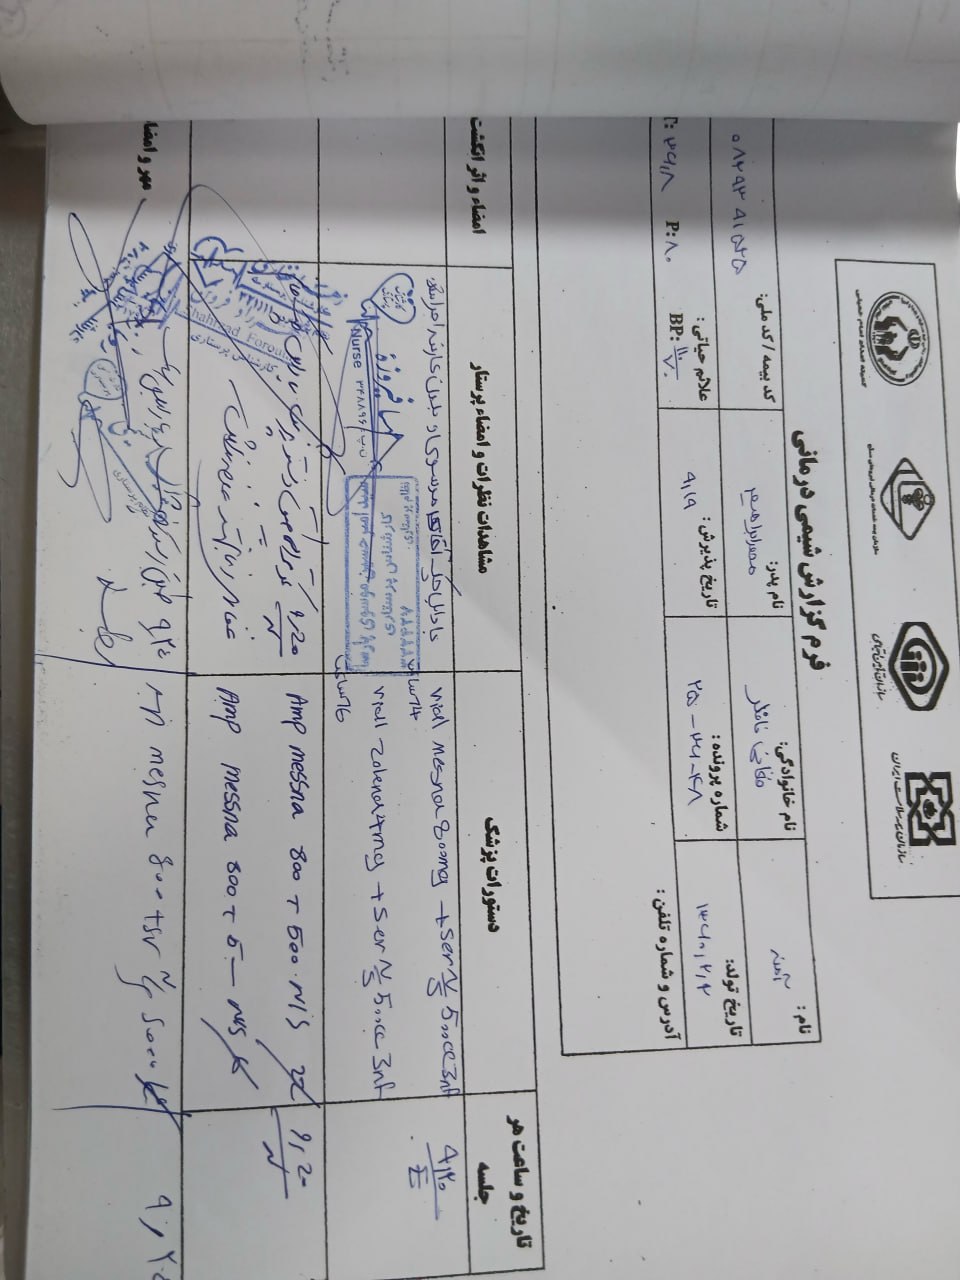

به ترتیب؛ روز ها: ۱۹ آبان, ۲۸ آذر, ۲۹ آذر, ۳۰ آذر

به ترتیب؛ روز ها: ۱۹ آبان, ۲۸ آذر, ۲۹ آذر, ۳۰ آذر

۱۹ آذر

۱۹ آذر

به ترتیب؛ روز ها: ۲۸ آذر, ۲۹ آذر, ۳۰ آذر, ۱ دی

۱ دی